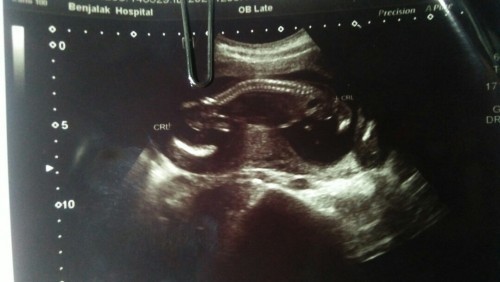

ท้องแรกค่ะ 17+5. สัปดาห์ ไปซาวครั้งแรก หมอไห่ใบนี้มา อยากรุ้ว่า เด็กอยู่ตรงไหน. ใครมีประสบการณ์ ช่วยบอกทีค่ะ หมอไม่อธิบายอะไรเลย